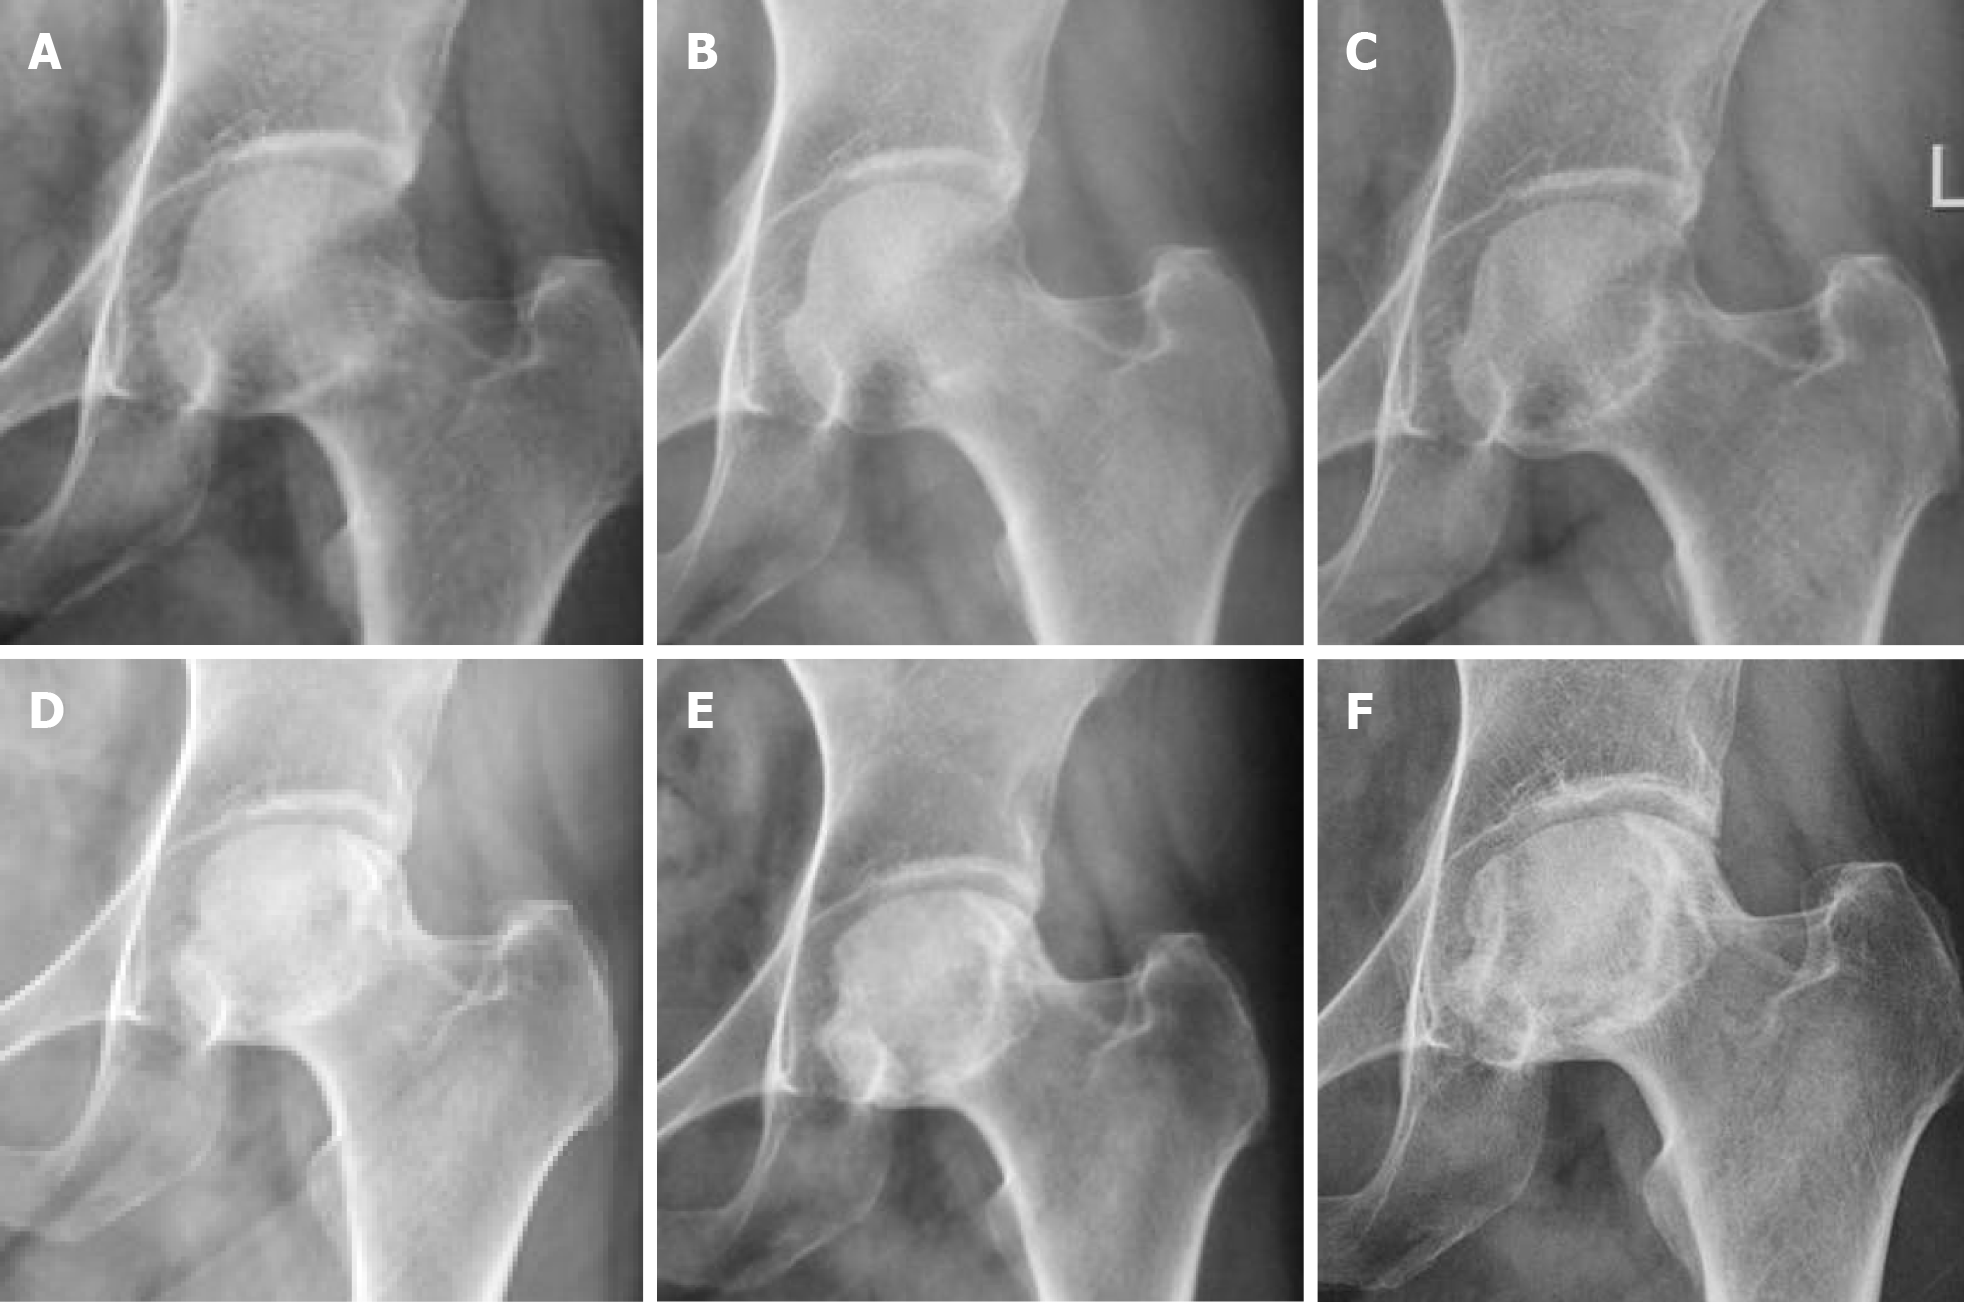

Figure 2

Figure 2 Left hip joint anterior-posterior X-ray. A: Left hip pain for 3 months (initial visit); B: At 16 months; C: At 3.5 years; D: At 5 years; E: At 6.5 years; F: At 10 years.